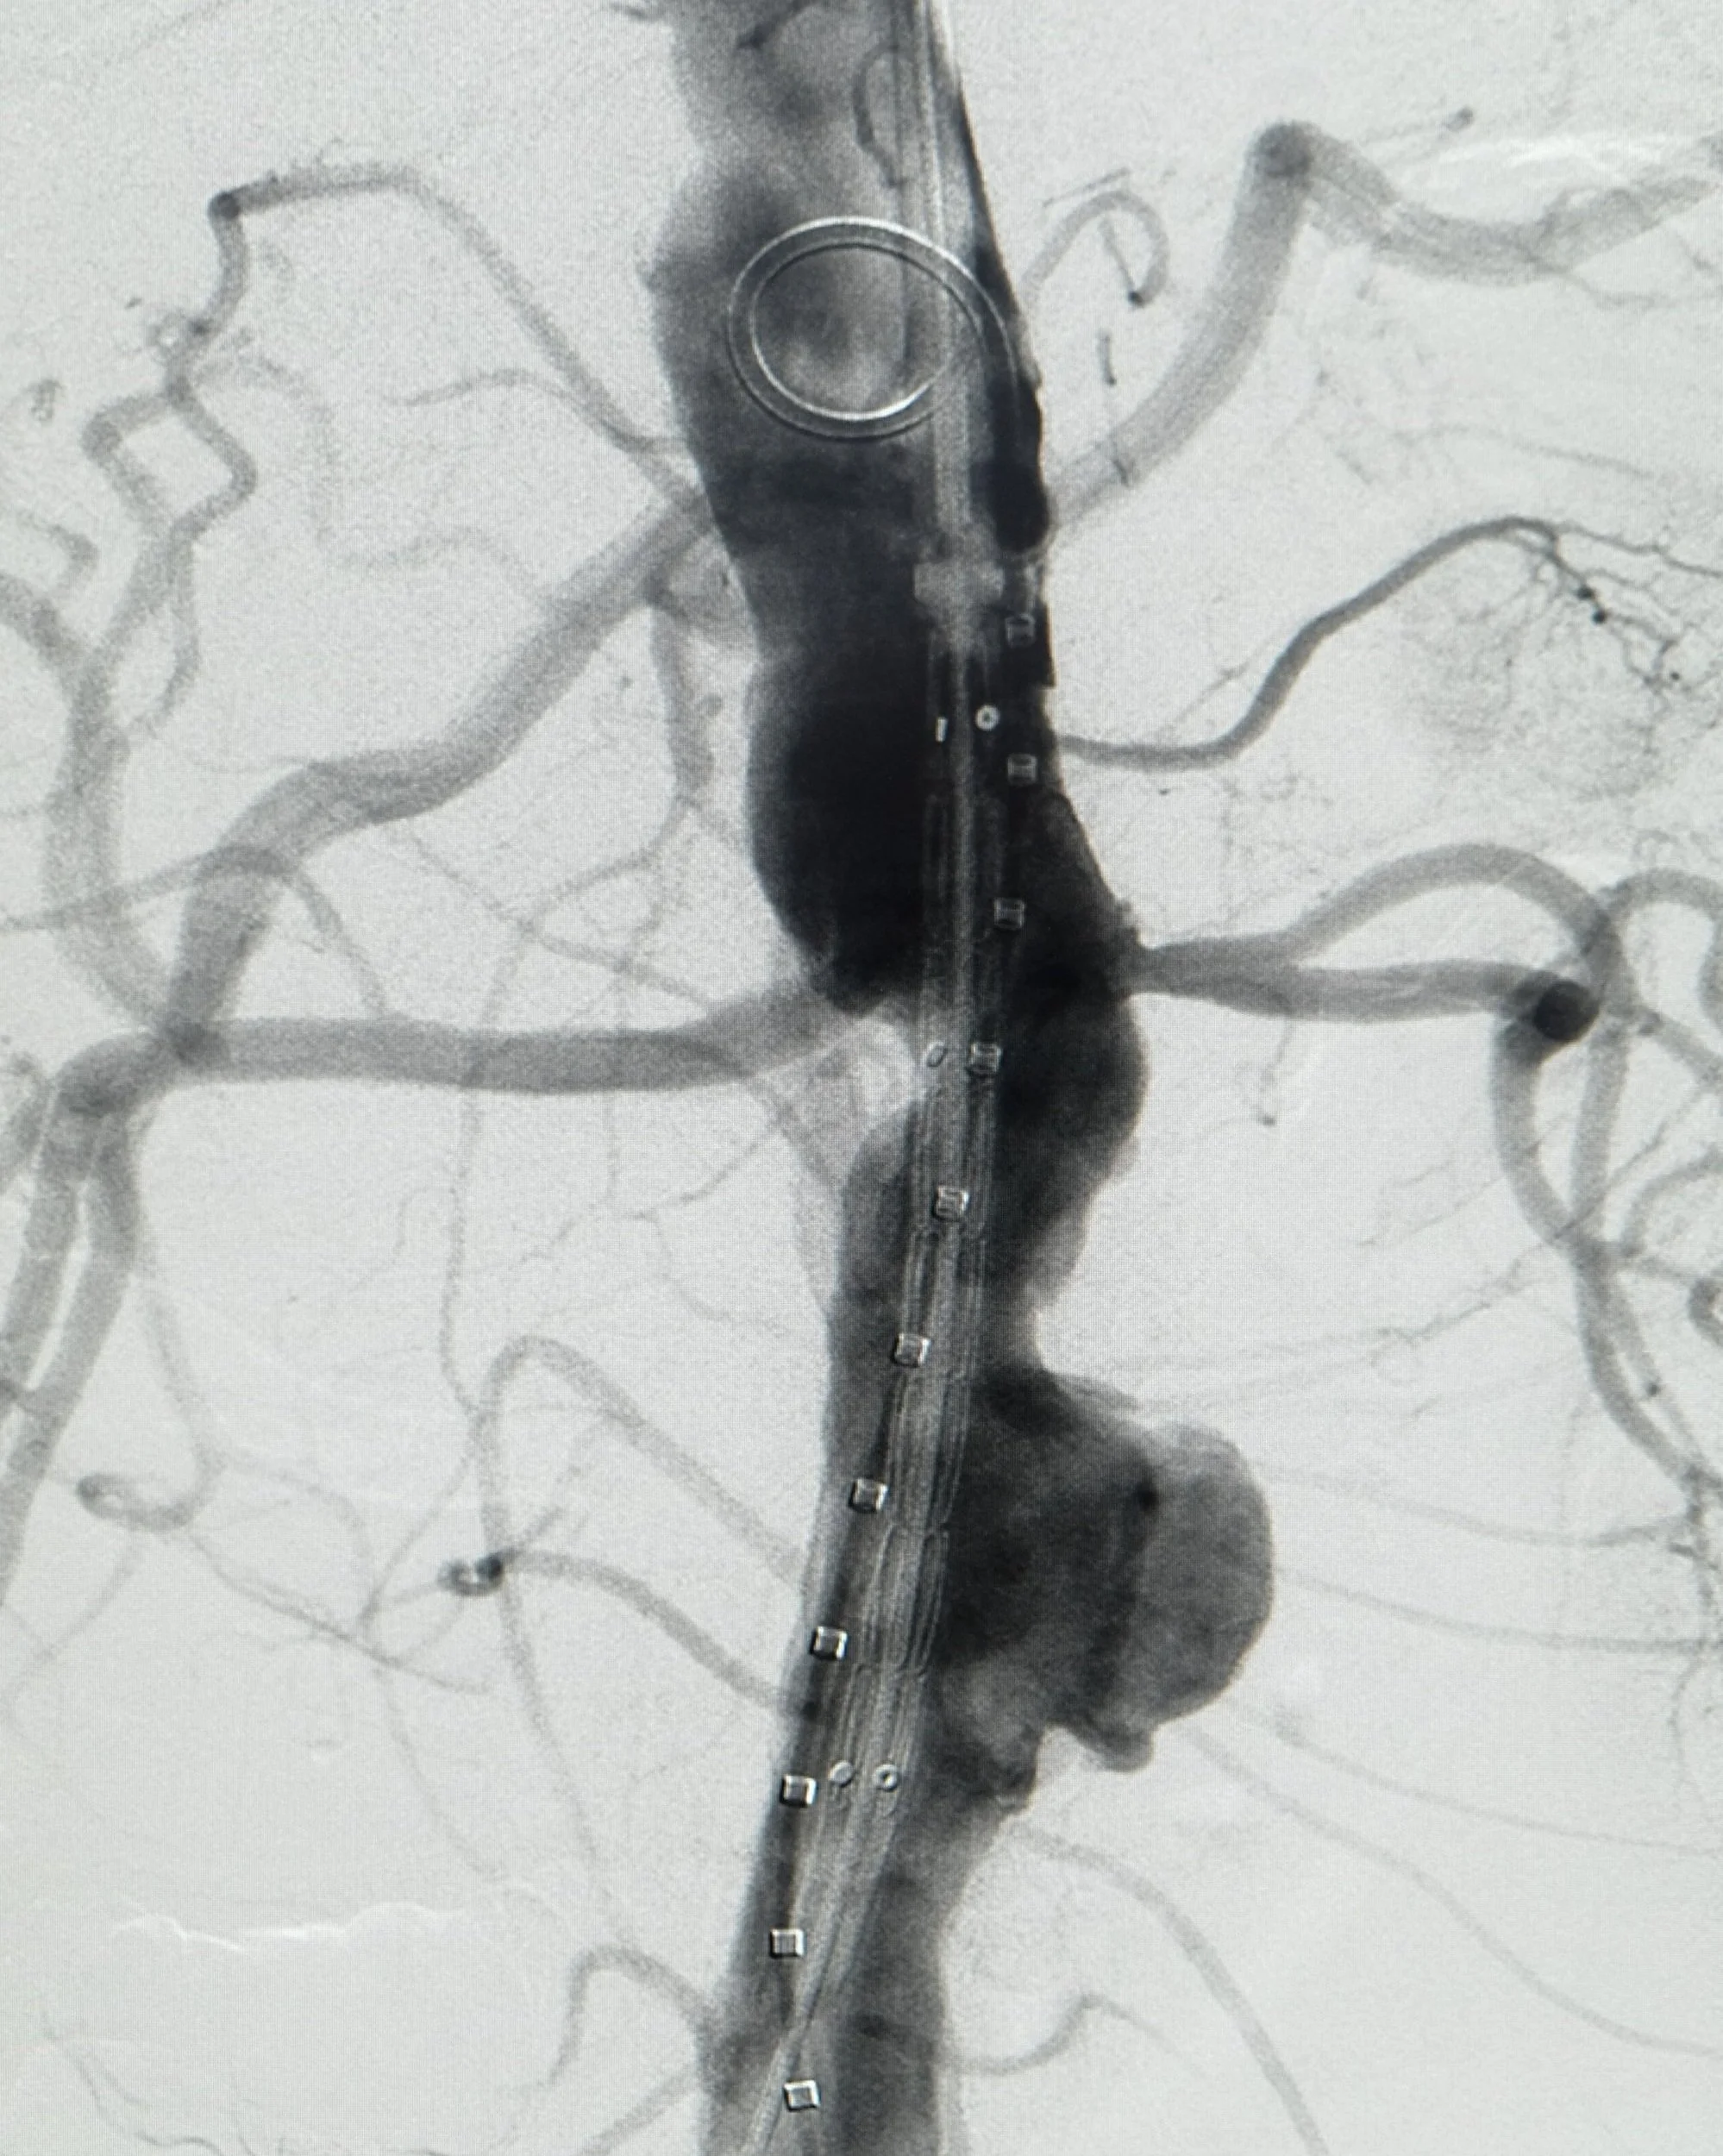

• Thoraco-abdominal endovascular devices

Example of communications campaign developed for GORE Medical.